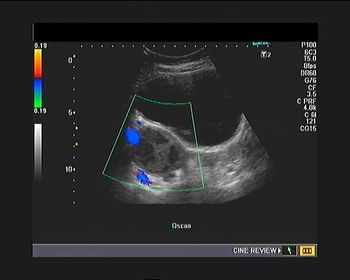

What is your diagnosis in this woman who presents with right hemipelvis pain?